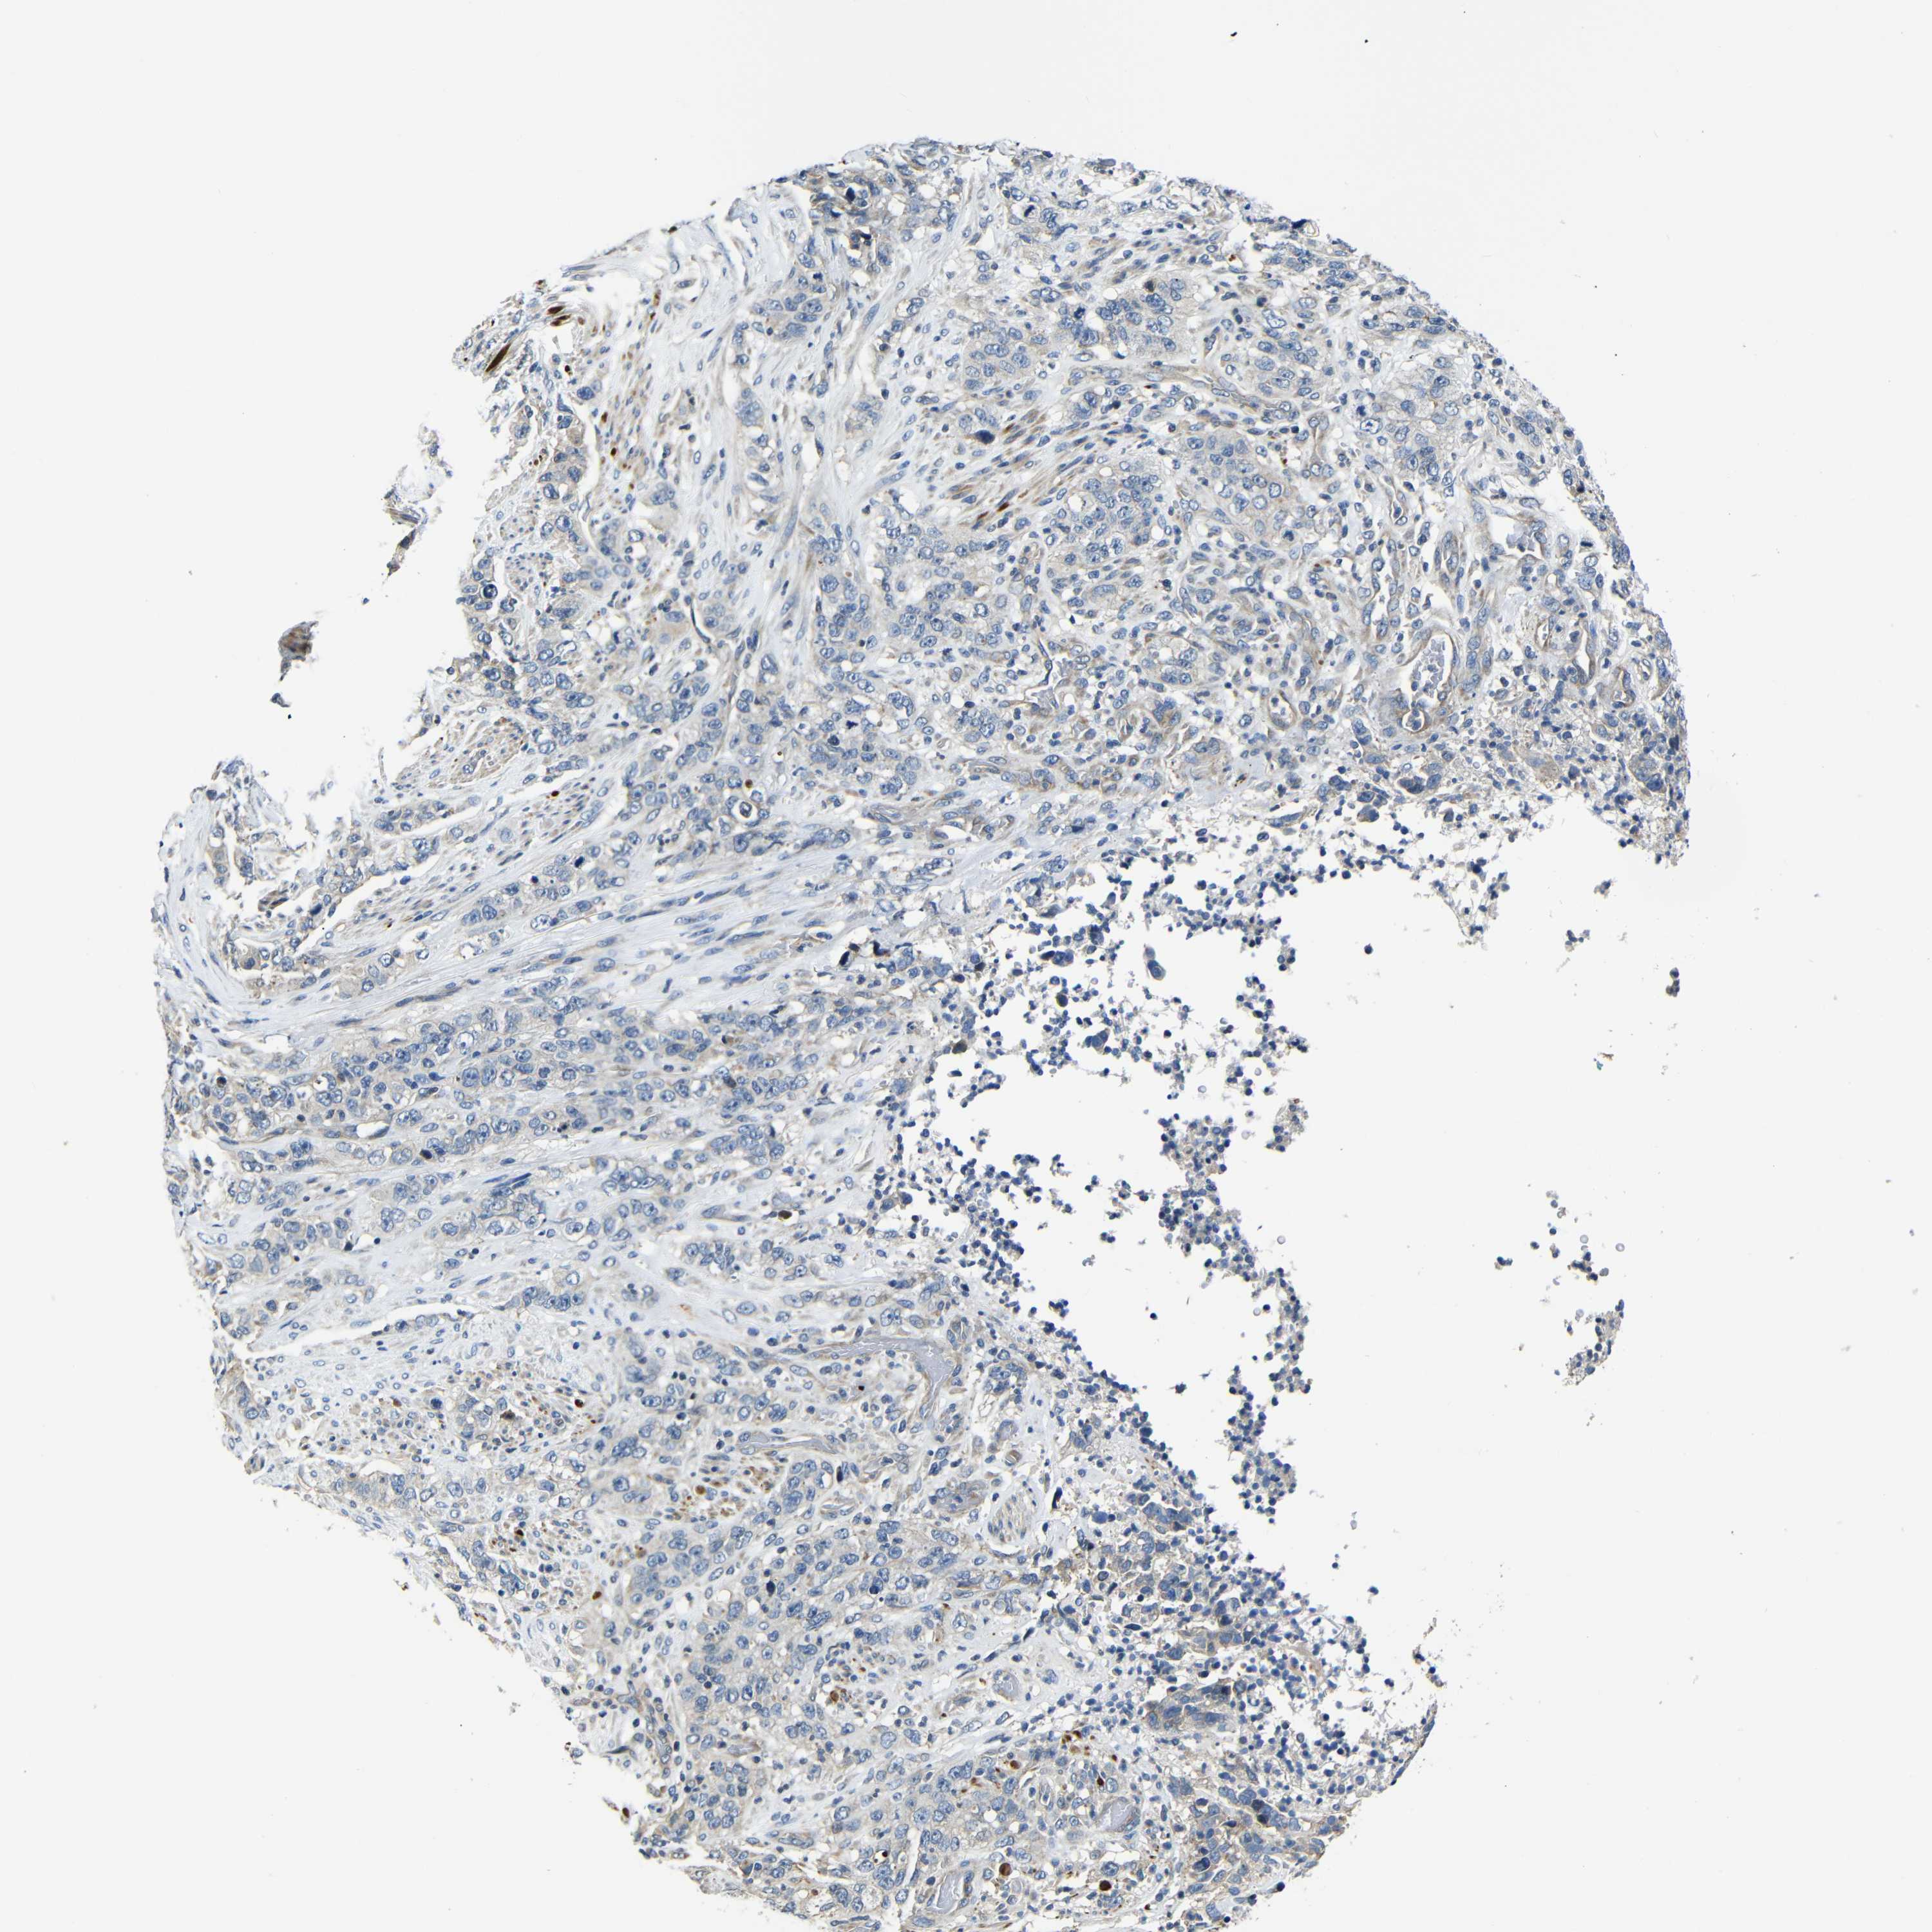

STOMACH CANCER - Protein expressioni

A mouse-over function shows sample information and annotation data. Click on an image to view it in a full screen mode. Samples can be filtered based on level of antibody staining by selecting one or several of the following categories: high, medium, low and not detected. The assay and annotation is described here.

Note that samples used for immunohistochemistry by the Human Protein Atlas do not correspond to samples in the TCGA dataset.

Antibody stainingi

Antibody staining in the annotated cell types in the current human tissue is reported as not detected, low, medium, or high, based on conventional immunohistochemistry profiling in selected tissues. This score is based on the combination of the staining intensity and fraction of stained cells.

Each image is clickable and will lead to virtual microscopy that enables deeper exploration of all samples and also displays staining intensity scores, fraction scores and subcellular localization as well as patient and tissue information for each sample.

HPA030212

HPA030213

HPA030214

HPA030215

CAB013496

Staining

High

Medium

Low

Not detected

Intensity

Strong

Moderate

Weak

Negative

Quantity

>75%

75%-25%

<25%

None

Location

Nuclear

Cytoplasmic/membranous

Cytoplasmic/membranous,nuclear

Adenocarcinoma, NOS